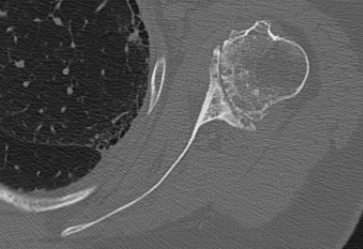

Walch classification glenoid morphology

Type A - centred humeral head, concentric wear, no humeral head subluxation

A1: minor central erosion

A2: major central erosion with humeral head protrusion

Type B - posterior subluxation of the humeral head, with biconcave glenoid and asymmetric wear

B1: narrowing of the posterior joint space

B2: biconcave glenoid with posterior rim erosion and retroverted glenoid

B3: monoconcave glenoid with > 15° retroversion or >70% posterior humeral head subluxation or both

Type C

C1: dysplastic glenoid with >25° retroversion

C2: biconcave, posterior bone loss, posterior translation of the humeral head

Type D: glenoid anteversion or anterior humeral head subluxation <40°

Type A2 Type B1

Type B2 Type B3

Type B3